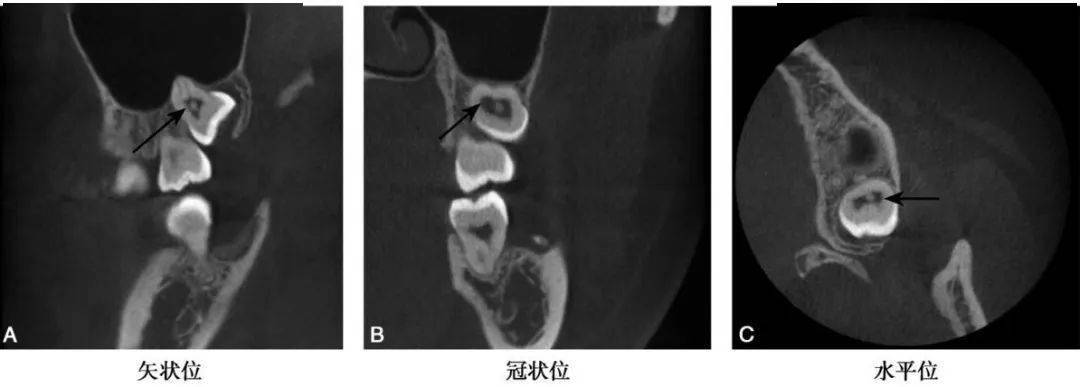

图1 B8髓腔髓石CBCT示B8髓腔内见一类圆形高密度阻射影(黑色箭头)

(1)髓石在髓腔中表现为不同形状的高密度团块影,形态与髓腔的形状有一定关系,后牙髓腔中的髓石可为圆形、卵圆形或不规则形(图1~3)。